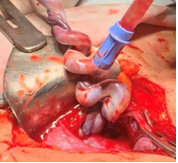

Mổ cấp cứu thành công sản phụ rau tiền đạo, mạch máu tiền đạo chảy máu

Sau 1 tuần theo dõi và điều trị tại khoa, ngày 29/4/2025 tình hình sản phụ đột ngột chuyển biến xấu, ra máu âm đạo nhiều hơn, bệnh nhân được chuyển lên khoa Đẻ cấp cứu. Qua thăm khám, hội chẩn, thai phụ được chẩn đoán: Thai 34 tuần - Rau tiền đạo - Theo dõi mạch máu tiền đạo, Trưởng khoa Đẻ cùng ekip đã tiến hành mổ cấp cứu cho sản phụ. Ca phẫu thuật thành công với bé trai nặng 2000g cất tiếng khóc chào đời.

Mạch máu tiền đạo thường kèm với tỷ lệ tử vong thai nhi rất cao và thường không được phát hiện cho đến khi thảm họa xảy ra. Mạch máu tiền đạo thường kèm với dây rốn bám màng. Trong hầu hết trường hợp, dây rốn bám màng và mạch máu tiền đạo không được phát hiện cho đến khi bánh rau và dây rốn được kiểm tra ở giai đoạn sau sinh. Siêu âm đen trắng và Doppler màu có thể chẩn đoán được hai tình trạng này trước sinh nhằm cung cấp thông tin cho các nhà lâm sàng để mang lại kết quả tốt hơn cho thai.

Mạch máu tiền đạo là một tình trạng hiếm gặp trong đó các mạch máu của thai nhi chạy trên màng rau, nằm gần hoặc đi qua lỗ trong cổ tử cung.

Thai nhi có thể bị mất máu dẫn đến tử vong trong vòng vài phút khi vỡ mạch máu này do cổ tử cung mở, vỡ ối hay bị ép giữa thai nhi và khung chậu.